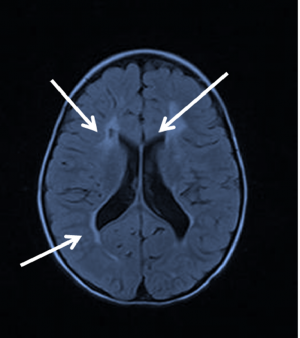

CT and MRI help to differentiate between the degree of possible optic nerve involvement, and suspected cortical involvement, and can help provide clues about prognosis and visual recovery. The extent and location of brain damage is important. MRI is always recommended in children with low APGAR scores.[20]

The presence of acute brain injury seen on brain MRI attributed to hypoxic-ischemia is now considered a significant feature of CVI, as per a recent task force on neonatal encephalopathy. Severity of visual impairment may be predicted by the clinical severity of HIE shown at birth. The pattern of lesions on MRI can be broadly classified into 3 categories: periventricular leukomalacia, diffuse cerebral atrophy, and multi-cystic encephalopathy.

Children with periventricular leukamalacia, encephalic cyst and diffuse cerebral atrophy are much less likely to have significant gains in visual function, while children with mild damage on MRI are more likely to have a better prognosis.